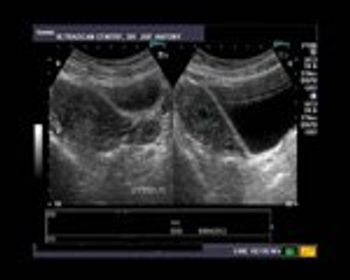

When a graafian follicle ruptures to release an oocyte, it is transformed into a corpus luteum. The corpus luteum is lined by a layer of granulose cells which rapidly become vascularized; some of these thin-walled vessels can rupture. This causes bleeding into the corpus luteum, resulting in the formation of a hemorrhagic cyst of the ovary.

This case is of a young married female patient of 25 years age. She presented with bleeding per vagina and mild pain in the right side of the pelvis.